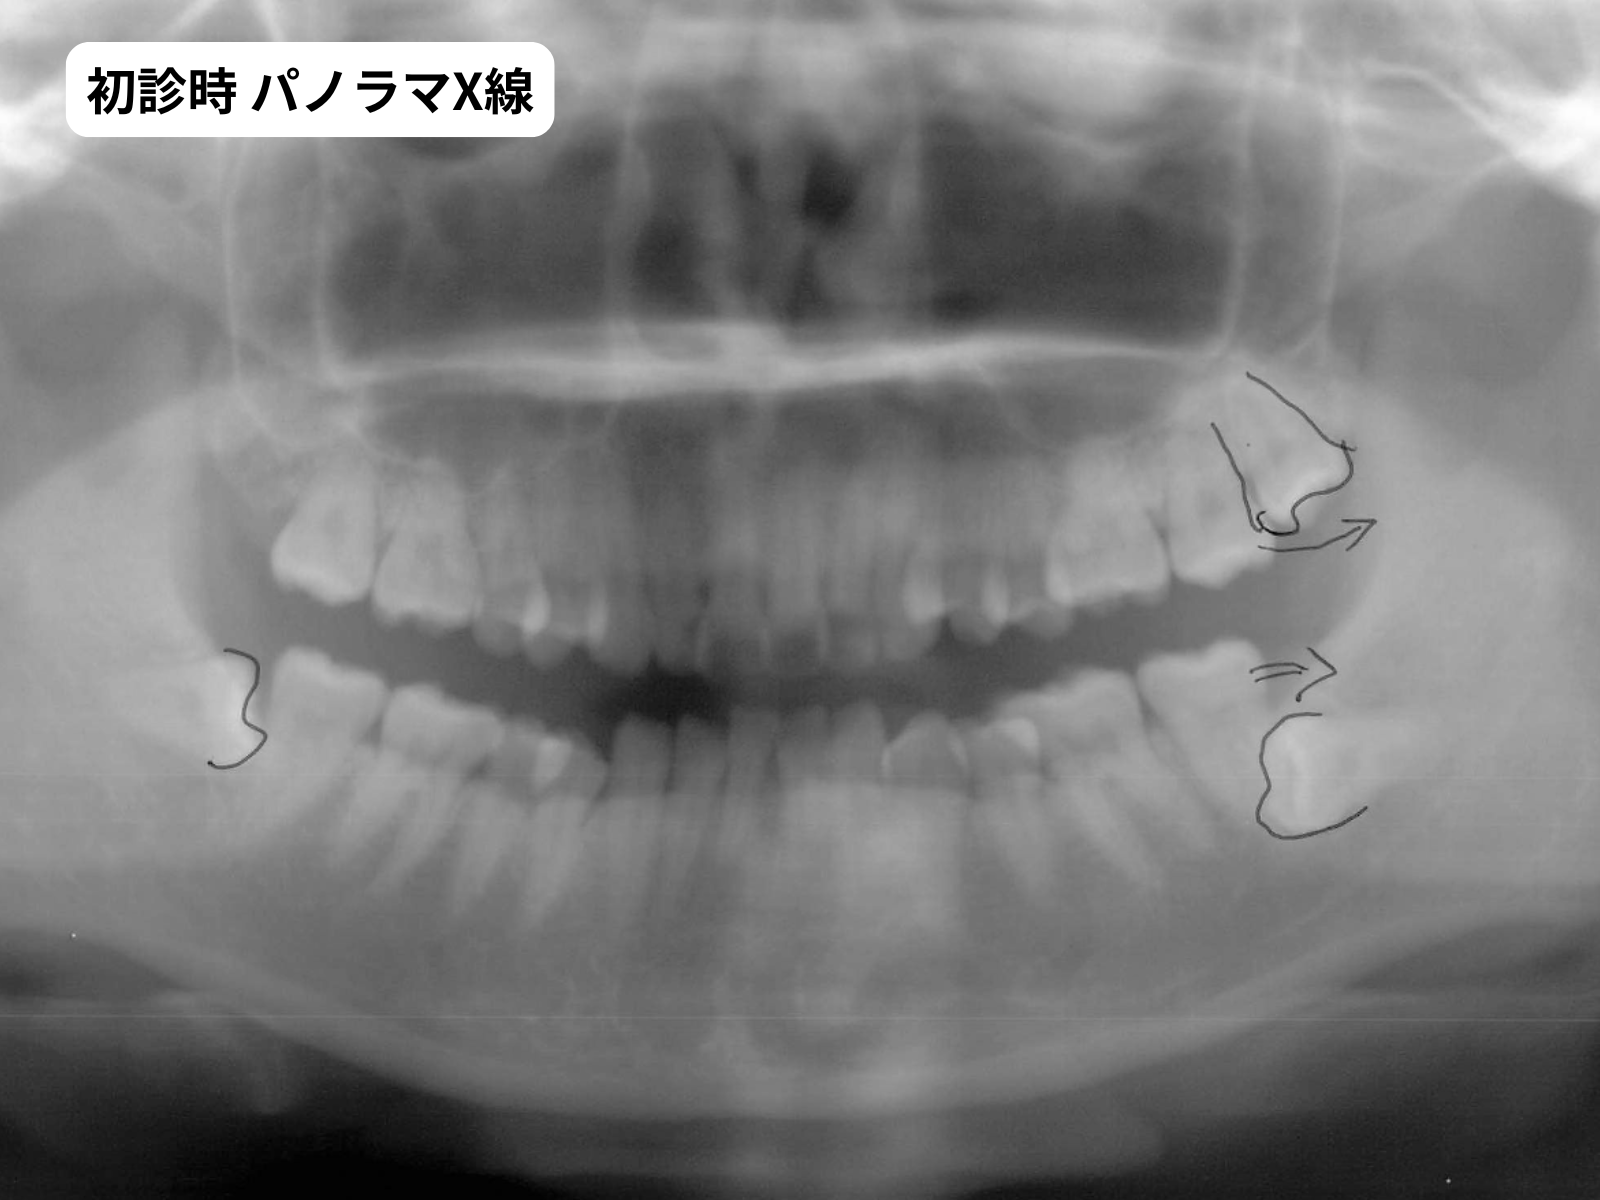

セファロトレース・パノラマX線(治療判断の根拠)

パノラマ 初診時パノラマX線|右下1番先天欠如|奈良の矯正歯科

5枚法で過蓋咬合の重度さ右下1番の欠損が確認できます。セファロトレースでは、骨格がローアングル傾向であること、過蓋咬合の原因が歯槽性であることが数値で示されました。これらを総合してマウスピース×非抜歯という判断に至りました。